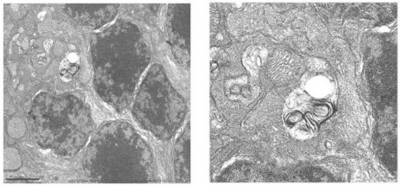

Acumulación de autofagosomas en retinas de ratones deficientes en Igf1. (Foto: UAM)

“Hemos encontrado que estos ratones presentan una inflamación crónica en la retina, con una importante activación de la microglía que se ve atenuada mediante la activación del flujo autofágico a los 6 meses de edad”, explica Ángela Martínez Valverde, coautora del trabajo y perteneciente al Centro de Investigación Biomédica en Red de Diabetes y Enfermedades Metabólicas Asociadas (CIBERDEM).

“Sin embargo, en ratones envejecidos de 12 meses de edad se produce un bloqueo de la autofagia que resulta en un aumento del número de autofagosomas en la retina. Este hecho, unido a otros procesos como la activación persistente de la microglía y del sistema inflamosoma, contribuye de manera importante a las alteraciones estructurales de la retina y a la pérdida de la función visual de los ratones deficientes en Igf1 durante el envejecimiento”, añade Isabel Varela-Nieto, también coautora, e investigadora del Centro de Investigación Biomédica en Red de Enfermedades Raras (CIBERER).